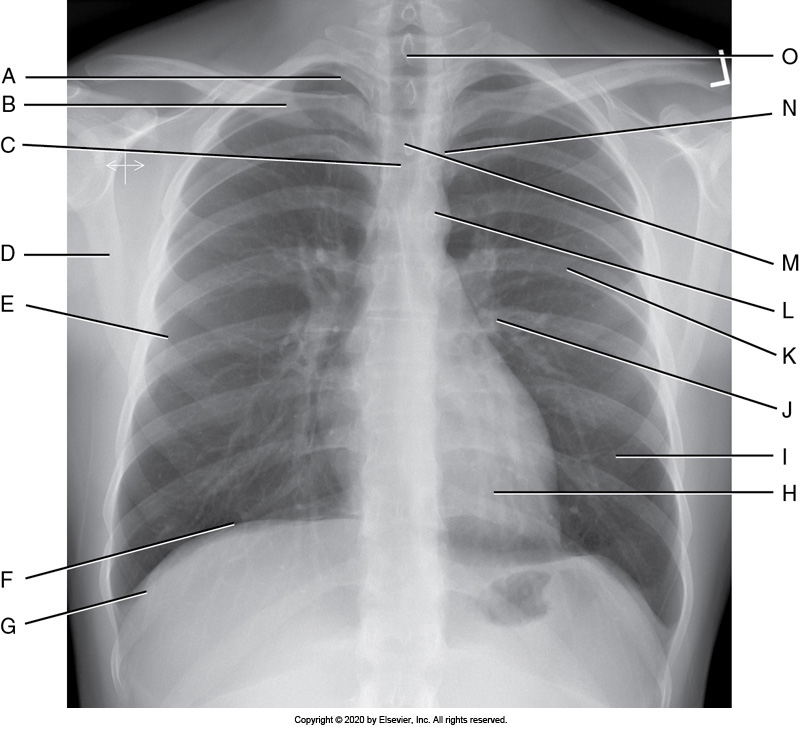

A PA chest projection with accurate positioning demonstrates

1. 10 posterior ribs above the diaphragm.

2. equal posterior ribs length on both sides of the chest.

3. the manubrium superimposed by the fourth thoracic vertebra.

4. the scapulae outside the lung field.

1, 2, 3, and 4

1 and 3 only

2 and 4 only

1, 2, and 4 only

Identify the labeled anatomy " G" on the PA chest projection

Scapula

Clavicle

Lung apex

Costrophenic angle